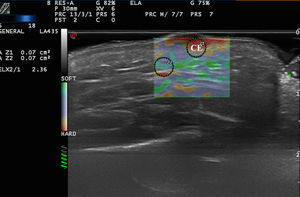

En el estudio de Bhatia et al.22 se evaluaron 52 masas cervicales no adenopáticas mediante elastografía cualitativa en tiempo real. El diagnóstico de las lesiones fue corroborado luego mediante citología e histología. Las lesiones fueron evaluadas de manera semicuantitativa y se estableció un escala de 0 a 3 (0 completamente blando - 3 completamente duro). Los lipomas presentaron menor rigidez que el resto de lesiones, la mayoría de ellas quistes, malformaciones y tumores neurogénicos (fig. 4). En una extensión del estudio realizado mediante elastografía SW23, en el que incluyeron tumores malignos y benignos cervicales, los tumores benignos presentaron una rigidez media de 226,4kPa, que fue estadísticamente superior a la rigidez media de las lesiones benignas (28,3kPa). El punto de corte de 174,4kPa tenía una sensibilidad del 83,3% y una especificidad del 97,5% para diferenciar ambos tipos de lesiones. Los autores aclaran que todos los tumores fueron correctamente diagnosticados mediante ecografía convencional, y que la elastografía no habría alterado el tratamiento de las lesiones, aunque en el caso de exploradores con menos experiencia, podría ser de ayuda en el diagnóstico de lesiones cervicales.

En el estudio de Park et al.24, la elastografía permitió diferenciar los quistes epidermoides inflamados frente a los intactos (fig. 4b), ya que estos últimos presentaban una mayor dureza.